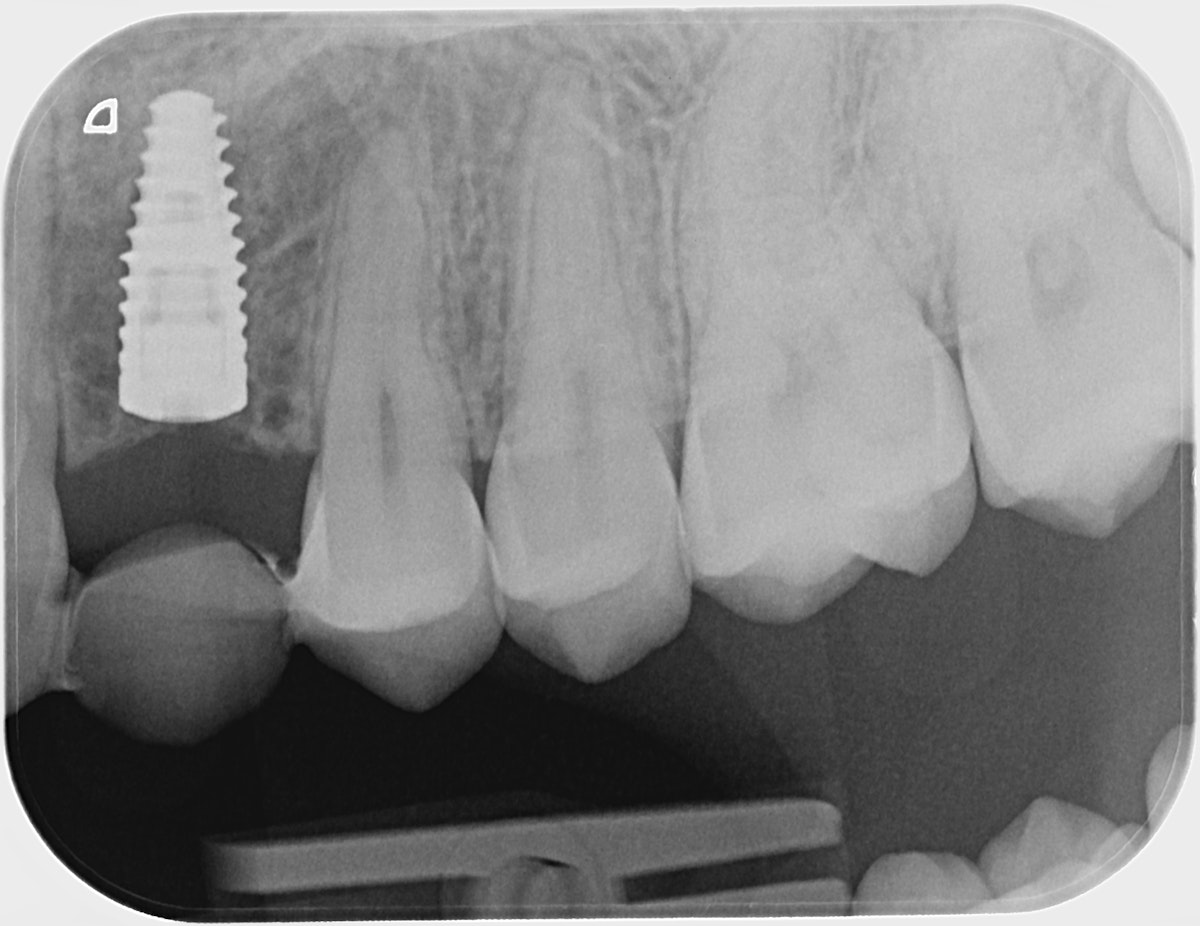

Radiologinen näkymä lopputilanteesta. Implanttikruunut paikoillaan.

Sama tilanne toiselta puolelta